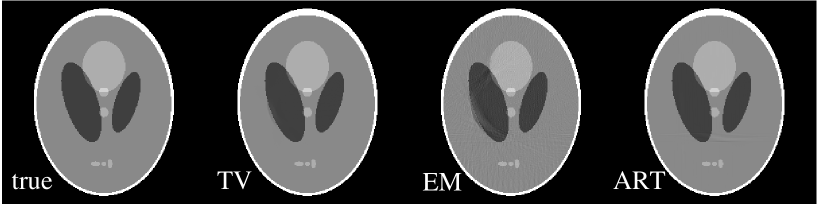

We apply the TV algorithm to reconstructing images from data shown in Fig. 8, which are generated at 150 views uniformly distributed over 209∘. The detector at each view contains 512 bins, of which the data of 30 bins have been discarded as shown in Fig. 8. Again, in this case there may be enough data to determine the image, because the number of non-zero projection measurements is 58,430. The question is whether or not the corresponding linear system is stable enough that the solution can be found.

We display in Fig. 9 images reconstructed by use of the TV, EM, and ART algorithms. Once again, the TV image is visually indistinguishable from the true image, and both EM and ART algorithms yield in this case quite accurate images. In this study, the TV algorithm appears to be more robust than the EM and ART algorithms, because the TV image is obtained with only a 100 iterations while both the EM and ART algorithms required 10000 iterations to achieve the image accuracy shown in Fig. 9. We note that the previous FT-TV algorithm cannot address the bad bins problem directly even in the parallel-beam case, because it is not possible to perform the FT of the detector data at each view when there is a gap.